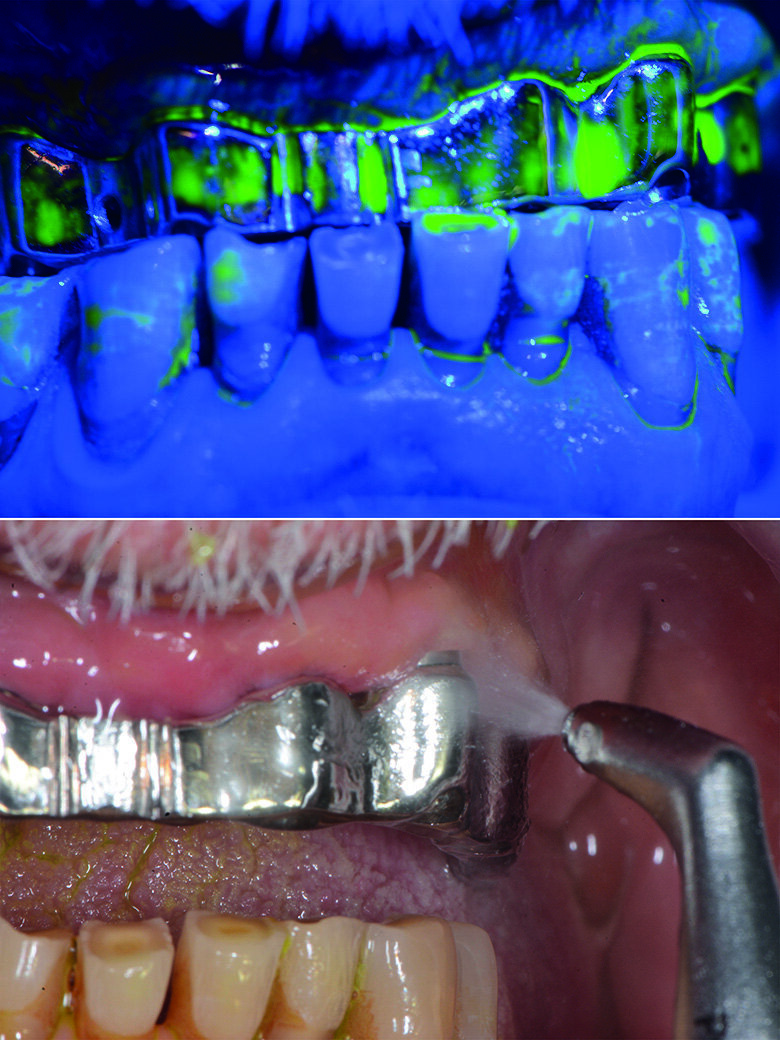

Documentiamo fotograficamente il cavo orale. Abbiamo mostrato al paziente, in real time, al fine di motivarlo a un più efficace controllo di placca domiciliare, i siti maggiormente interessati dall’accumulo di placca nel cavo orale, compresi, il dorso della lingua e gli spazi interprossimali e la barra implantare con l’aiuto del rilevatore di placca alla fluorescina Plac-o-Tect (Directa) (Fig. 10). Scegliamo per il paziente l’utilizzo corretto degli strumenti di igiene orale domiciliare – spazzolino e scovolino – più idonei alle sue esigenze strutturali, tissutali e anatomiche, alla manualità e alla predisposizione caratteriale alle differenti tecnologie manuali o meccaniche, come da tailored brushing method (Nardi et al., J Biomed, 2016).

Viene eseguito il deplaquing con approccio clinico D-Biotech (Dental Biofilm Detection Topographic Technique). L’operatore, dopo aver passato sulle superfici del cavo orale la spugnetta già intrisa di rivelatore di placca alla fluorescina Plac-o-Tect (Directa) osserva la topografia del biofilm batterico presente condividendola visivamente con il paziente in modo da avere un rinforzo motivazionale anche durante la seduta di igiene orale professionale. Questo approccio clinico permette di eseguire un lavoro efficace e minimamente invasivo, poiché consente all’operatore di strumentare con polishing selettivo, airpolishing o debridment con gli ablatori, esclusivamente seguendo la topografia del biofilm batterico con meno dispersione di glicina ed un timing ridotto dell’operatività (Fig. 13).